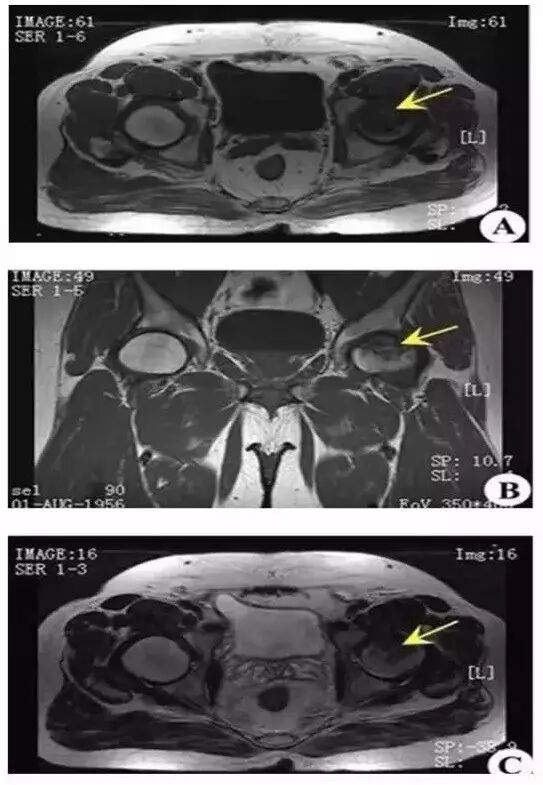

Ⅲ 期 股骨头变形,软骨下骨折、塌陷、新月体形成。T1 加权呈带状低信号,T2 加权示中等或高信号,为关节积液进入软骨下骨折线的裂隙。新月形坏死骨发生应力性软骨下骨折、塌陷并与关节软骨分离。由于纤维组织长入形成致密的无血管墙,使修复被阻挡,进入坏死骨的修复受限。

上图为Ⅲ期